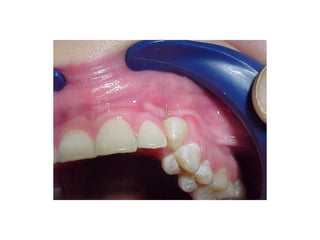

• Paciente de 25 años con

pérdida casi total de

dientes superiores y

prótesis mal adaptada.

• Ganchos que no

cumplen su función.

Modelos de estudio, a la izquierda sin la prótesis a la derecha con la prótesis, el

molar izquierdo con destrucción casi total de la corona y sin utilidad protésica.